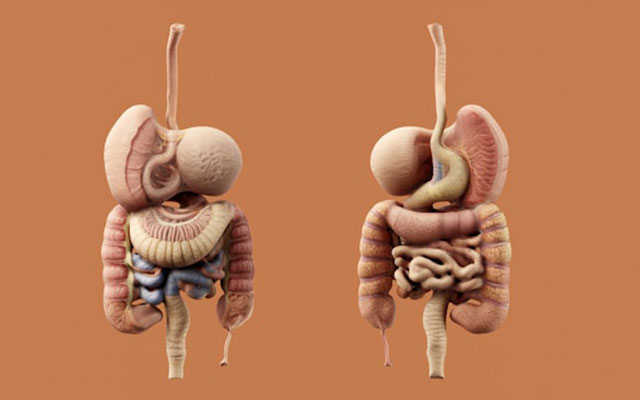

تخصصات متعددة

يقدم لكم مركزنا للتشخيص الطبي رعاية شاملة ومتخصصة.

نقدم لك تحاليل دقيقة وتشخيصات شاملة لمساعدة الأطباء على وصف العلاجات الأنسب لحالتك الصحية.

سواء كنتم بحاجة إلى استشارات طبية متخصصة أو تحاليل طبية سريعة أو فحوصات تصوير طبي متقدمة، فإن جميع التشخيصات الضرورية لصحتكم متوفرة في مكان واحد، مما يسهم في تسهيل مسار رعايتكم الطبية.